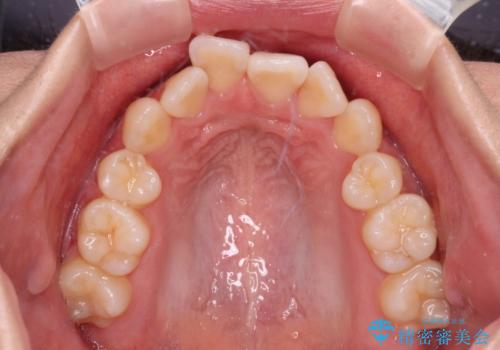

- 抜歯矯正の後戻りを気にして来院された患者様です。

舌の突出癖によるオープンバイトになっていたため、インビザラインによるマウスピース矯正をおすすめしましたが、自己管理の自信がないとのことで、ワイヤー装置による矯正治療を行うこととしました。

舌の突出癖が認められると、上下前歯の隙間を閉じることができません。

舌のトレーニングをしっかりと行っていただくことで、歯列を整えることができます。